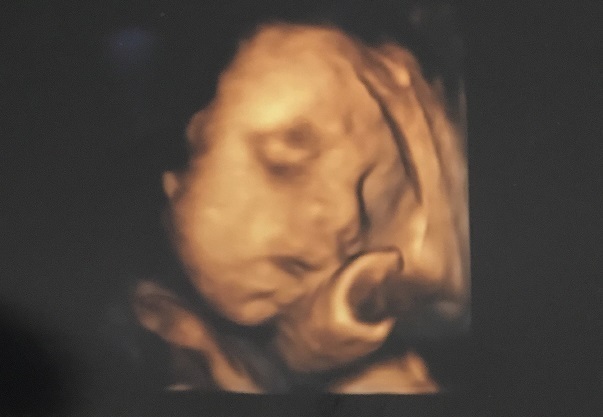

28週0日(28w0d・男の子)|こさち さん(31歳)

エコー写真撮影時のエピソード:

目、鼻、指が見えて、誰に似てるかな?という話をしたのを覚えています! 本当に自分のお腹の中に人間の赤ちゃんが入っているんだと不思議で神秘的な気持ちになり、とても感動したと同時にママになる実感が湧いてきました。